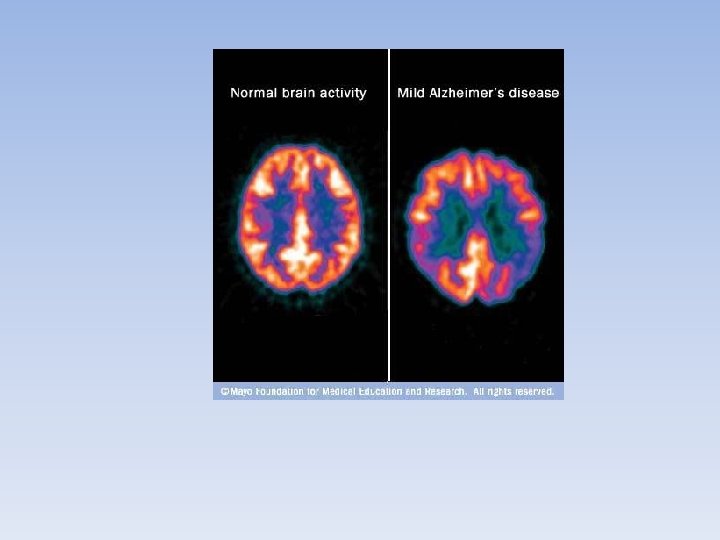

Positron Emission Tomography • Nuclear medicine that uses radioisotopes that emit particles called positrons. • Usually used to detect cancer in tissues, heart disease and some brain disorders such as Alzheimer’s disease.